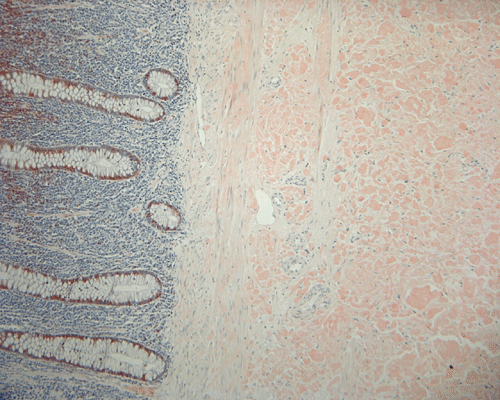

On low magnification, the mucosa appear intact and unremarkable. However, the submosa and muscular layer is replaced by a pale eosinophilic, hypocellular, amorphous material (Panel A). These material separate the smooth muscle bundles (Panel B and C). On Masson's trichrome, these material appears blue (Panel D). They are negative for elastic stain (Panel E). These material are stained orange by Congo Red stain (Panel F and G) which gives an apple green birefrigence on polarized light (Panel H). Electron microscopy was performed and revealed non-branhing straight fibrils ranging from 6.6 to 8.3 nm in diameter consistent with amyloid.

Immunohistochemistry was performed and showed strong reactivity for lambda light chain. Numerous plasma cells within the mucosa overlying the amyloid deposition are also postive for lambda light chains. The results suggest a monoclonal lambda light chain plasma cell dyscrasia but it could not be further classified in the excised specimen.